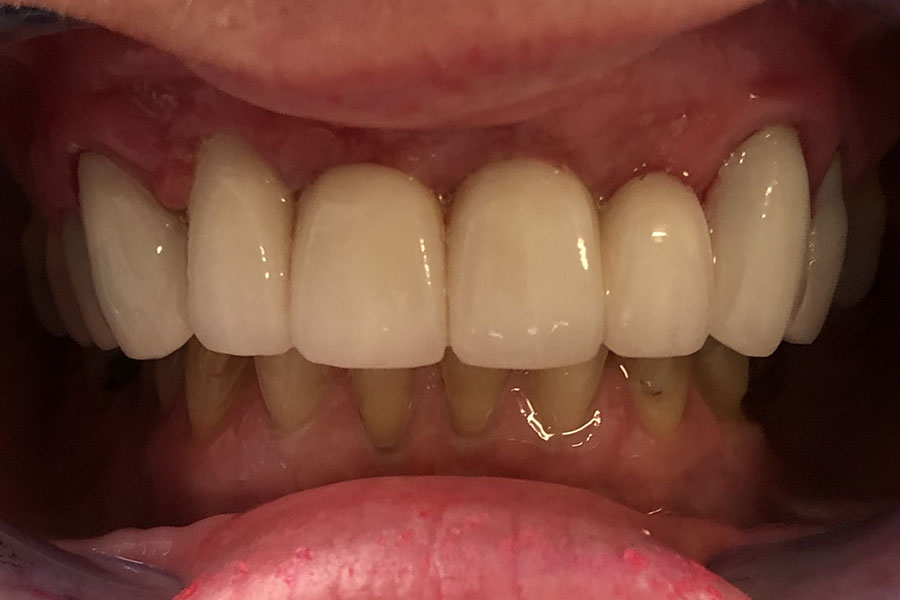

Simone has had a long span bridge to replace her missing four front teeth for over 30 years.

The admits that she never smiled confidently as the teeth did not look natural. The two teeth supporting the bridge on either side wore off around the gums due to the excessive stress from the long span bridge.

The bridge was removed and the four missing teeth in the middle were replaced with the support of two dental implants. The worn out supporting teeth were restored with individual crowns. It seems obvious that Jenni is quite confident with her new smile.